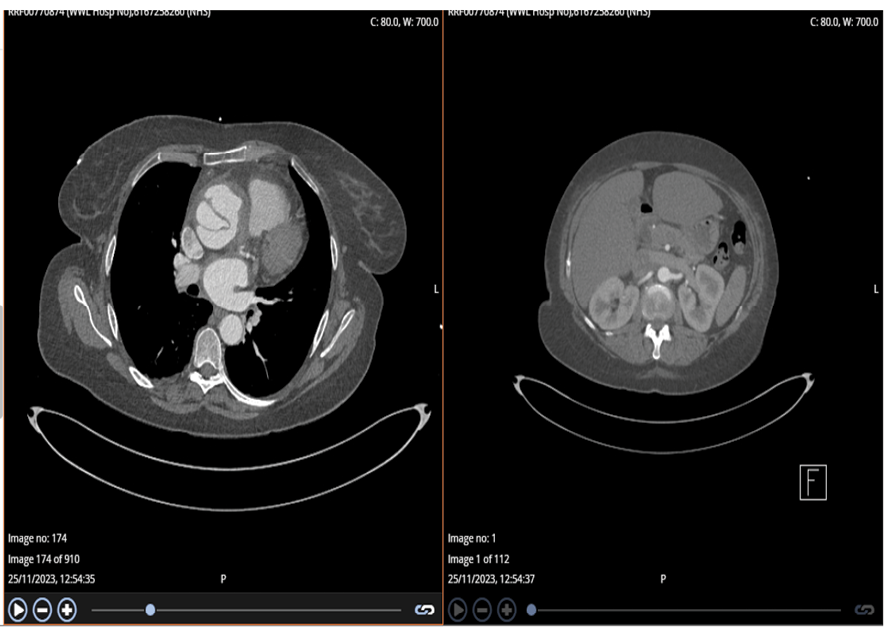

A follow-up CTA performed the following day (Figure-4) confirmed a complex Stanford type A aortic dissection with concurrent aneurysmal dilatation, measuring 6.4 cm at its widest point and affecting both the ascending aorta and aortic root. Notably, the right coronary sinus and artery were supplied by the false lumen, which clarified why the initial attempt to engage the RCA during the angiogram was unsuccessful. The dissection flap ended just before the innominate artery, with all three major cranial vessels receiving blood from the true lumen. The rest of aorta appeared normal, with no signs of contrast extravasation, and only a small right pleural effusion was noted.

Figure 4. Abdominal and Aortic CT on second day of first presentation diagnosed Aortic dissection

Figure 5. CTA whole Aorta at second presentation confirmed previously diagnosed aortic dissection